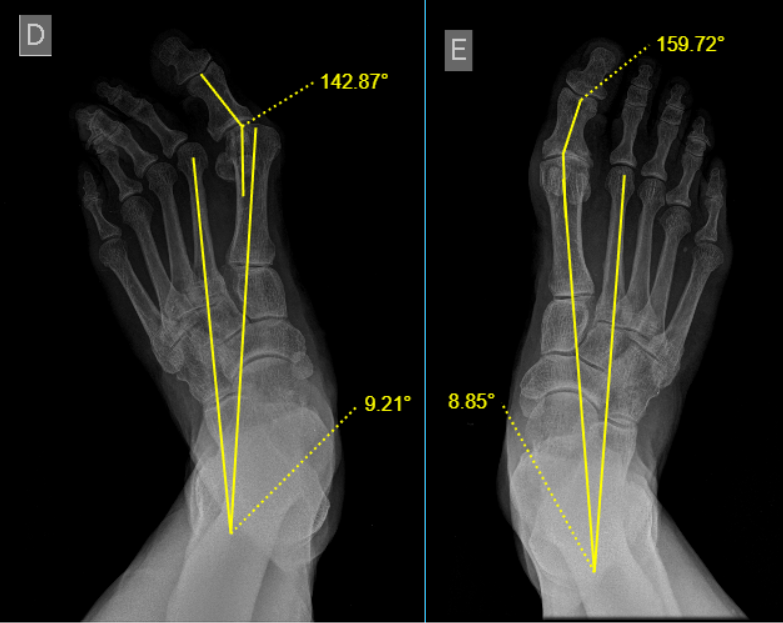

Exames de imagem, como radiografia, podem ser solicitados para avaliar o grau da deformidade e auxiliar na escolha do tratamento e definição de técnica cirúrgica. É importante ainda obter dados sobre as condições de saúde do paciente, tais como doenças reumatológicas, neurológicas e vasculares, diabetes, infecções fúngicas nos pés, alterações degenerativas de outras articulações e alinhamento do retropé.

A escolha da técnica depende da gravidade da deformidade e das necessidades do paciente. Para definição de um plano cirúrgico leva-se em consideração: idade e nível de atividade do paciente, doenças associadas, capacidade de correção da deformidade, instabilidade e grau de degeneração articular, necessidade de correção das deformidades combinadas entre outros fatores.